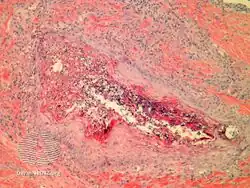

Perforating folliculitis is a skin condition in humans characterized by discrete follicular keratotic eruptions involving mainly the hairy parts of the extremities.[1]: 539–540

- Perforating folliculitis/pathology